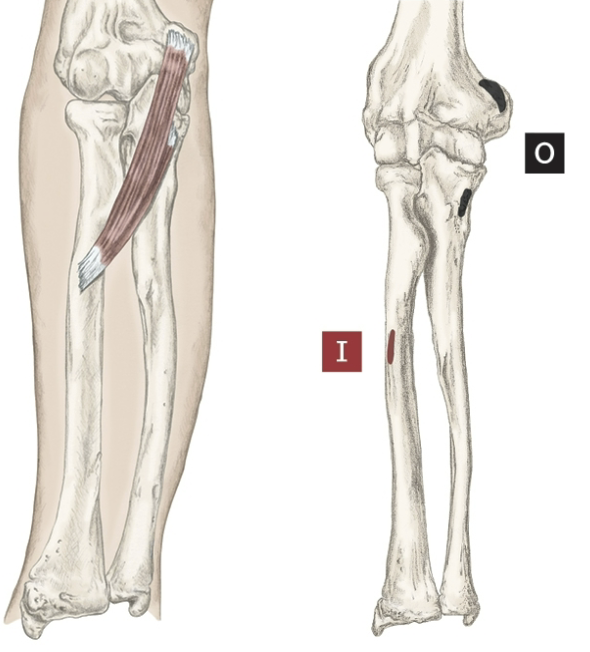

Action of Flexor Digitorum Profundus

Flexion of 2-5 fingers [ MCP,PIP,DIP]

Origin of Flexor Digitorum Profundus

Proximal ulna and anterior, and medial

Insertion of Flexor Digitorum Profundus

Base of palmar surface of distal phalanges 2-5

Nerve that the Flexor Digitorum Profundus innervates

Median Nerve